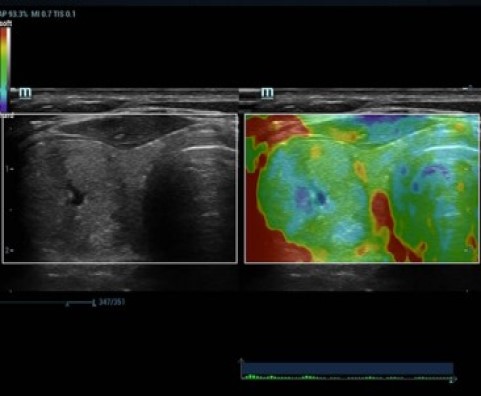

Эластография Sound Touch

Тканевой трекинг

Перфузия яичника

Поджелудочная железа

Фолликулы

Эластография щитовидной железы